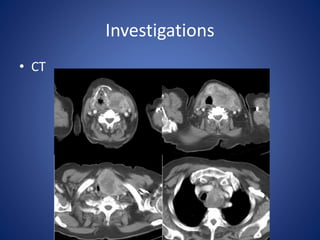

Investigations

• CT